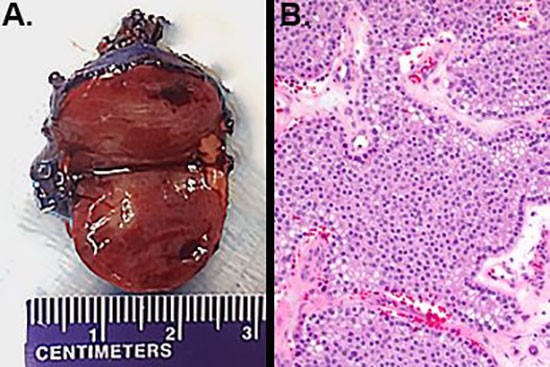

The parathyroid tumor was abnormally adherent to the thyroid gland, but was not pale colored, firm, or fibrotic. Due to concern for possible rupture of the parathyroid tumor during the course of mobilization, as well as for the possibility of parathyroid carcinoma, the left lobe of the thyroid was resected with the enlarged parathyroid gland. The patient was admitted overnight for electrolyte monitoring due to his risk for hungry bone syndrome. Postoperatively, he did well, and was discharged home on 600 mg of elemental calcium three times daily, in addition to daily vitamin D3. His calcium levels decreased from 11.8 mg/dL immediately postoperatively to 9.9 mg/dL on postoperative day one, and then to 8.8 mg/dL on postoperative day three. Pathologic examination demonstrated a 2.6 cm hypercellular parathyroid with decreased intracellular fat (Figure 3), consistent with parathyroid adenoma, with no evidence of malignancy.

Figure 3. a) Gross pathology demonstrated a 2.6 cm parathyroid tumor. b) On hematoxylin and eosin staining, the parathyroid tumor was hypercellular, with decreased intracellular fat. No rim of normal parathyroid tissue was identified (200 X magnification).